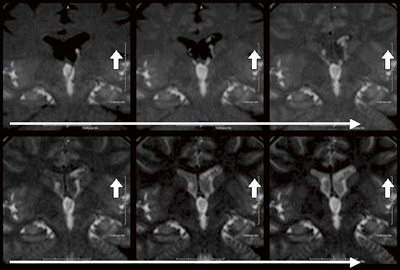

●造影剤を使わずにCSF-flowを描出

造影剤を使用せずに,電波によるラベリング(Time-SLIP法)によって脳脊髄液の動きを画像化することができ,東海大学・山田晋也先生から先駆的論文が発表されました1)。この方法による特発性正常圧水頭症(iNPH)への応用が期待されています。1.5Tでは,すでに臨床現場で実際に試みられています(図3)。

図3 非造影にて描出されたCSF-flow(1.5T MRI)